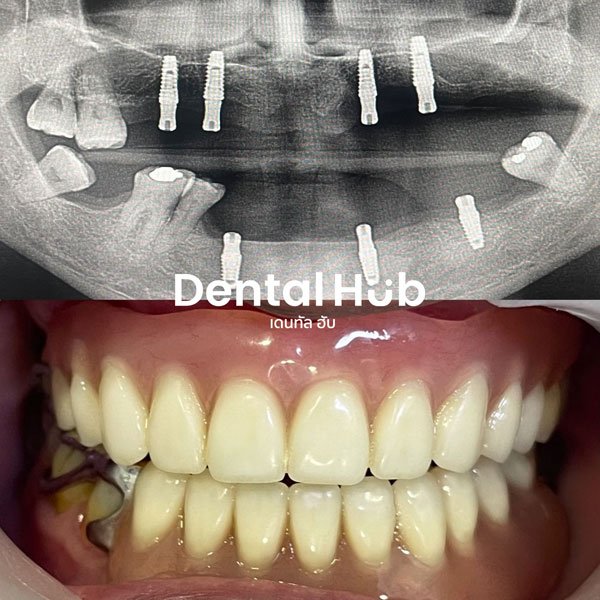

รากฟันเทียม เป็นฟันปลอมแบบติดแน่น โดยฝังแกนไททาเนี่ยมซึ่งเป็นวัสดุที่เข้ากับเนื้อเยื่อร่างกายได้ดี ลงในกระดูกบริเวณช่องว่างที่ไม่มีฟัน และทำตัวครอบฟันต่อสวมบนรากฟันเทียมเพื่อใช้บดเคี้ยวและความสวยงาม

เคสฟันปลอมเสริมรากฟันเทียม

ระบบดิจิทัล การรักษาที่แม่นยำที่สุด

ในเคสที่ซับซ้อน ทางคลินิกมีระบบการฝังร่วมกับการวางแผนสามมิติผ่านคอมพิวเตอร์ ทำให้การรักษา

1. ตรวจวางแผนการรักษาในช่องปากและเอกซเรย์

2. ฝังรากเทียมตามแผนการรักษา

3. ตัดไหม 2 สัปดาห์หลังฝังรากเทียม

4. นัด 3 เดือน เพื่อพิมพ์ปากทำครอบฟัน

5. ใส่ครอบฟัน